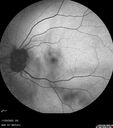

Elmiron (pentasosan polysulfate) Macular Toxicity104 views77 year old female who had been on Elmiron for 20 years and stopped it 2 years agoMar 15, 2026